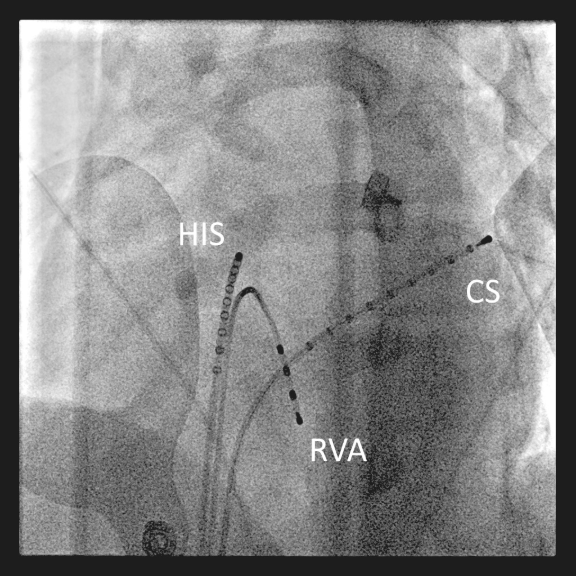

Fluoroskopisches Bild einer typischen Lage intrakardialer Katheter für eine diagnostische EPU.

Abbildung 1: Fluoroskopisches Bild (LAO 40°) einer typischen Lage intrakardialer Katheter für eine diagnostische EPU. Ein zehnpoliger Katheter ist in Position des His-Bündels (HIS), ein vierpoliger Katheter im rechtsventrikulären Apex (RVA) und ein weiterer zehnpoliger Katheter im Coronarsinus (CS) positioniert.